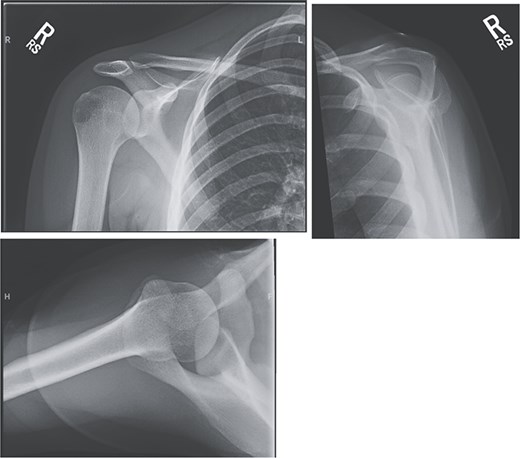

An 18-year-old, right-hand dominant woman presented reporting several weeks of right shoulder pain limiting participation in DIII collegiate volleyball. Examination revealed atrophy of the infraspinatus region. Muscle testing revealed weakness of infraspinatus and supraspinatus with reproducible symptoms. Radiographs were without transverse scapular ligament calcification (Fig. 1). Magnetic resonance imaging (MRI) arthrogram revealed low-grade undersurface fraying of the supraspinatus and infraspinatus tendons consistent with impingement, hypertrophic posterior inferior labrum, and no evidence of paralabral cyst (Fig. 2). Rest from hitting activities, anti-inflammatory medications, and periscapular strengthening therapy were initiated.

Initial MRI arthrogram revealed low-grade undersurface fraying of the supraspinatus and infraspinatus tendons consistent with internal impingement, hypertrophic posterior inferior labrum without visible tearing, and no evidence of paralabral cyst.